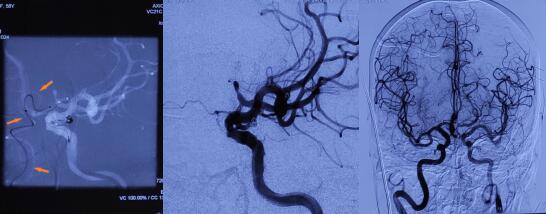

图1、2、3、4 术前CTA、DSA提示动脉瘤位置、与胚胎型大脑后动脉等相关血管关系及双侧迂曲的颈内动脉